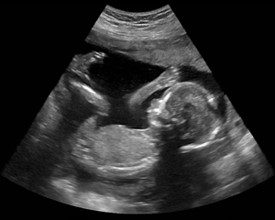

2D – podstawowy tryb projekcji dwuwymiarowego obrazu, wyświetlany w 256 stopniowej skali szarości.